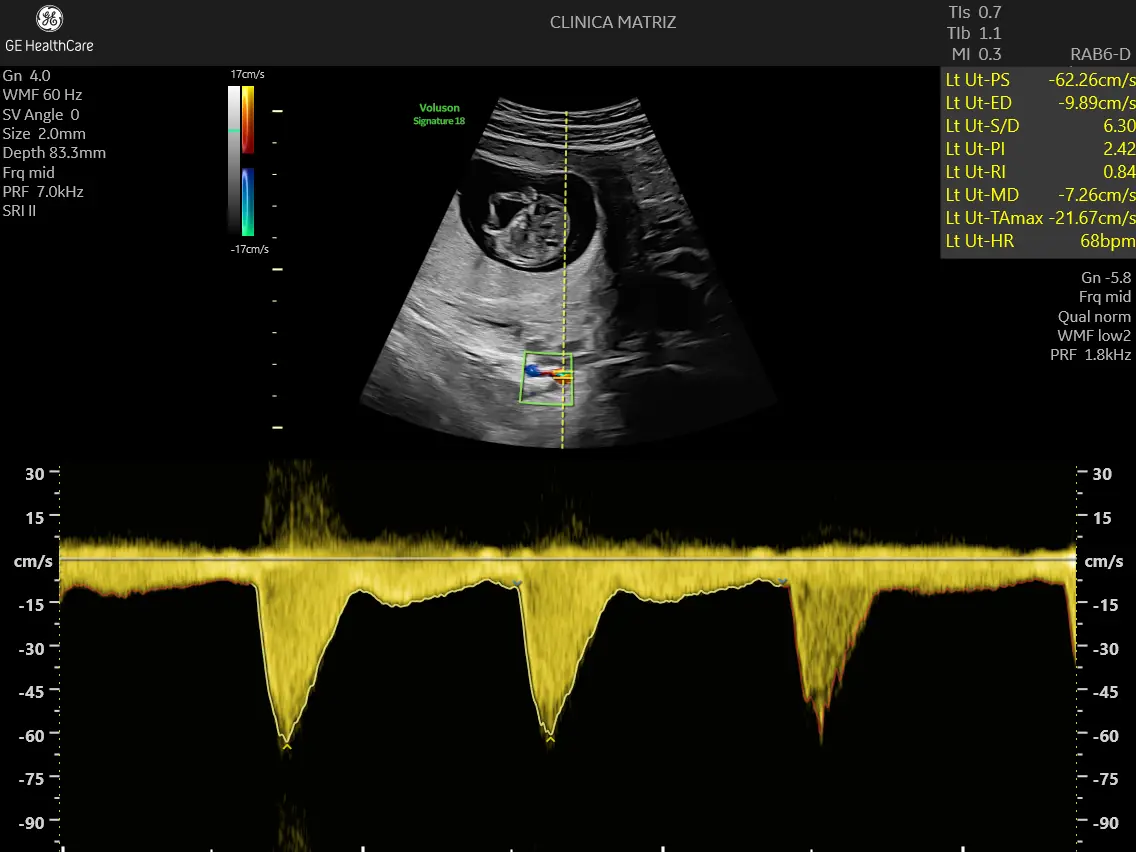

28–34 semanas (ou mais tarde, conforme indicação): ecografia do 3.º trimestre

Nesta fase, é comum avaliar:

- crescimento fetal e estimativa de peso (com a ressalva de que é uma estimativa);

- posição do bebé e localização da placenta;

- líquido amniótico;

- sinais que possam justificar vigilância adicional.

Quando há indicação clínica, pode associar-se o estudo com Doppler/fluxometria, que avalia fluxos sanguíneos e ajuda na vigilância do bem-estar fetal em contextos específicos.